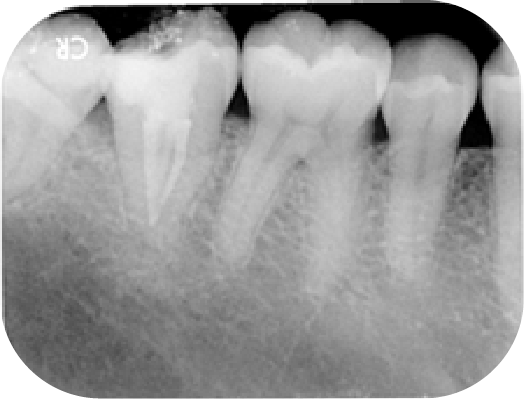

在台灣人的下排第二大臼齒有滿高的機率根管不會是一條一條而是一個C字形的樣子,這種牙齒醫師用肉眼看時只會是一團黑黑的洞,這時就需要用顯微鏡去仔細區分整個C字形裡有多少根管,才不會像是瞎子摸象一樣的去做治療

案例分享